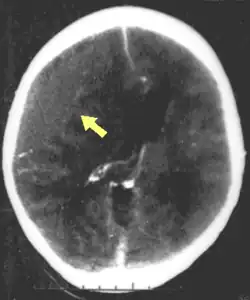

Hematomas, also focal lesions, are collections of blood in or around the brain that can result from hemorrhage.[11] Intracerebral hemorrhage, with bleeding in the brain tissue itself, is an intra-axial lesion. Extra-axial lesions include epidural hematoma, subdural hematoma, subarachnoid hemorrhage, and intraventricular hemorrhage.[38] Epidural hematoma involves bleeding into the area between the skull and the dura mater, the outermost of the three membranes surrounding the brain.[11] In subdural hematoma, bleeding occurs between the dura and the arachnoid mater.[23] Subarachnoid hemorrhage involves bleeding into the space between the arachnoid membrane and the pia mater.[23] Intraventricular hemorrhage occurs when there is bleeding in the ventricles.[38]

The preferred radiologic test in the emergency setting to determine the severity of a TBI is computed tomography (CT): it is quick, accurate, and widely available.[80] Follow-up CT scans may be performed later to determine whether the injury has progressed.[10]